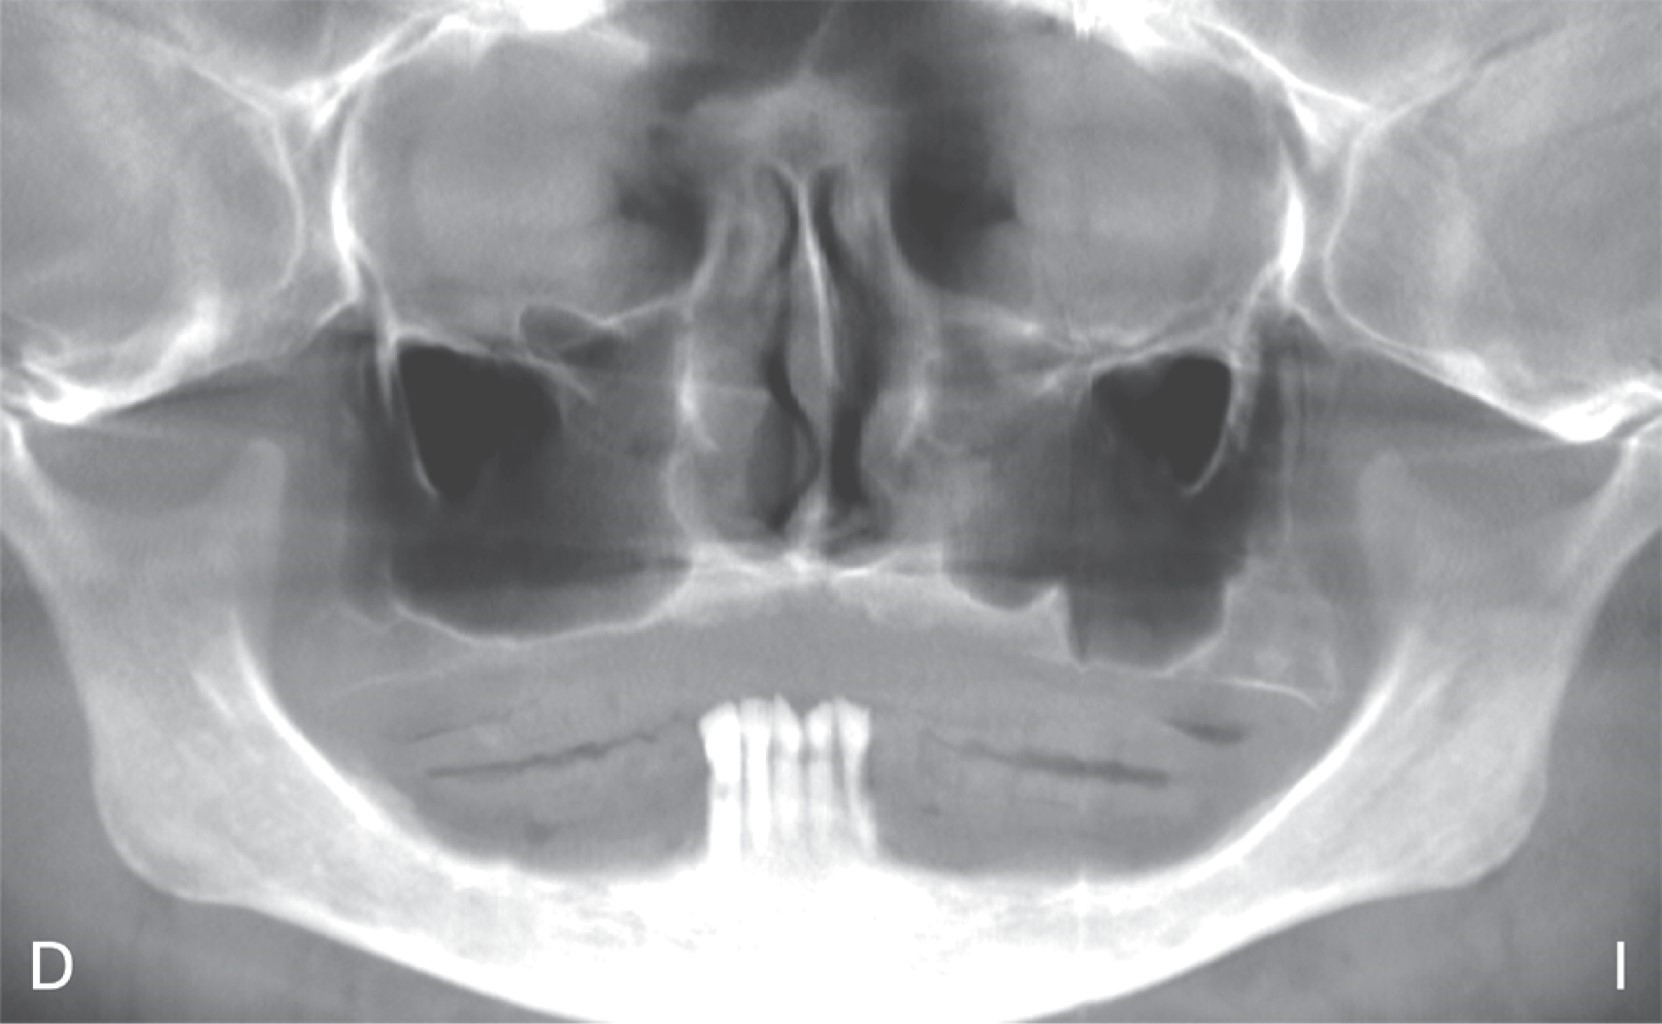

Vestibuloplasty with Er,Cr:YSGG laser and EPX biomolecule nanocarrier: a new periodontal healing agent.

Alveolar bone resorption often results in mucosal insertions interfering with the construction, stability and retention of a removable prosthesis, an option to modify this tissue is obtained by means of vestibuloplasty. Currently, wound healing can be promoted by using high power laser applied to oral surgical procedures. A case report of a female patient who underwent a vestibuloplasty procedure with laser Er,Cr:YSGG, using chitosan gel with EPX biomolecule nanocarriers postoperatively. A fast and favorable healing is observed when combining both therapeutics, besides, when using products with chitosan, the risk of necrosis of human gingival fibroblasts is reduced, as recently reported in the use of chlorhexidine mouthwashes.

Figure 2